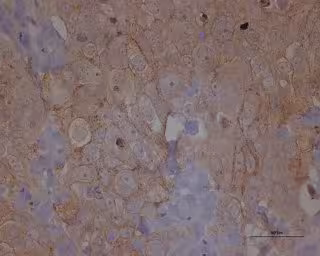

Metástasis cáncer de ovario

IDIBELL-ICO

Investigadores del Grupo de Señalización Molecular en Cáncer del 'Programa Oncobell' del Instituto de Investigación Biomédica de Bellvitge (IDIBELL) y del 'Programa ProCURE' del Instituto Catalán de Oncología (ICO), han identificado nueva diana terapéutica para combatir la metástasis en cáncer de ovario.

Concretamente, han logrado asociar la expresión del receptor CXCR4 en células tumorales de ovario a su potencial de diseminación a través del torrente sanguíneo. CXCR4 es un receptor implicado en el movimiento de las células de la sangre, especialmente en aquellas ubicadas en la médula ósea, que ya había sido relacionado anteriormente con procesos de diseminación en cáncer de mama.